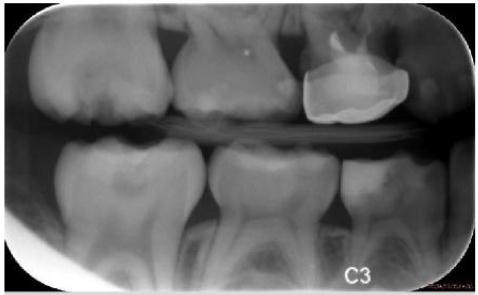

应用:医学图像分割(如 MITOS 数据集上的细胞分割)。